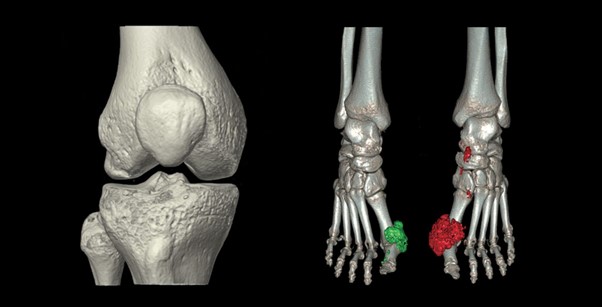

Khả năng chụp toàn bộ cơ thể phối hợp với công nghệ dựng hình 3D hiện đại giúp khảo sát tổn thương của nhiều cơ quan

- CT Scan xương khớp. Sử dụng trong các trường hợp chấn thương xương phức tạp, bệnh lý xương: Viêm xương, u xương, di căn xương, lao xương và bất thường bẩm sinh xương.

Ảnh dựng 3D bằng máy CT 160 lát Aquilion Prime SP